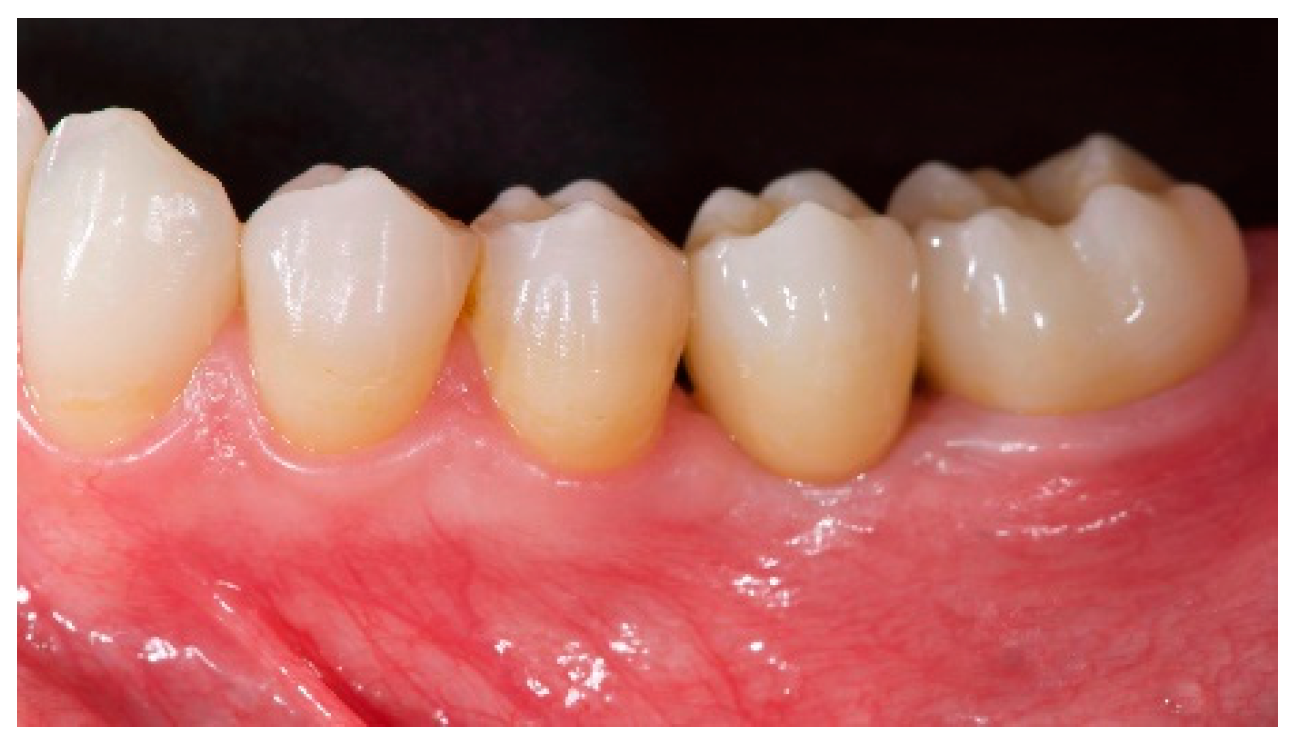

- The aesthetic evaluation was performed according to the pink aesthetic score (PES) on the vestibular and occlusal pictures taken including at least one adjacent tooth per side. The values were assessed at 6 and 12-months after loading follow-up examinations (18-months follow-up) [14] Seven variables (mesial papilla, distal papilla, soft-tissue level, soft-tissue contour, alveolar process deficiency, soft-tissue color and texture) were assessed with a 2-1-0 score (2 being best and 0 being poorest) by the same blinded dentist.

| PES (mm) | 8.2 ± 0.8 (95% CI 7.7–8.7) | 12.0 ± 0.7 (95% CI 11.5–12.5) |